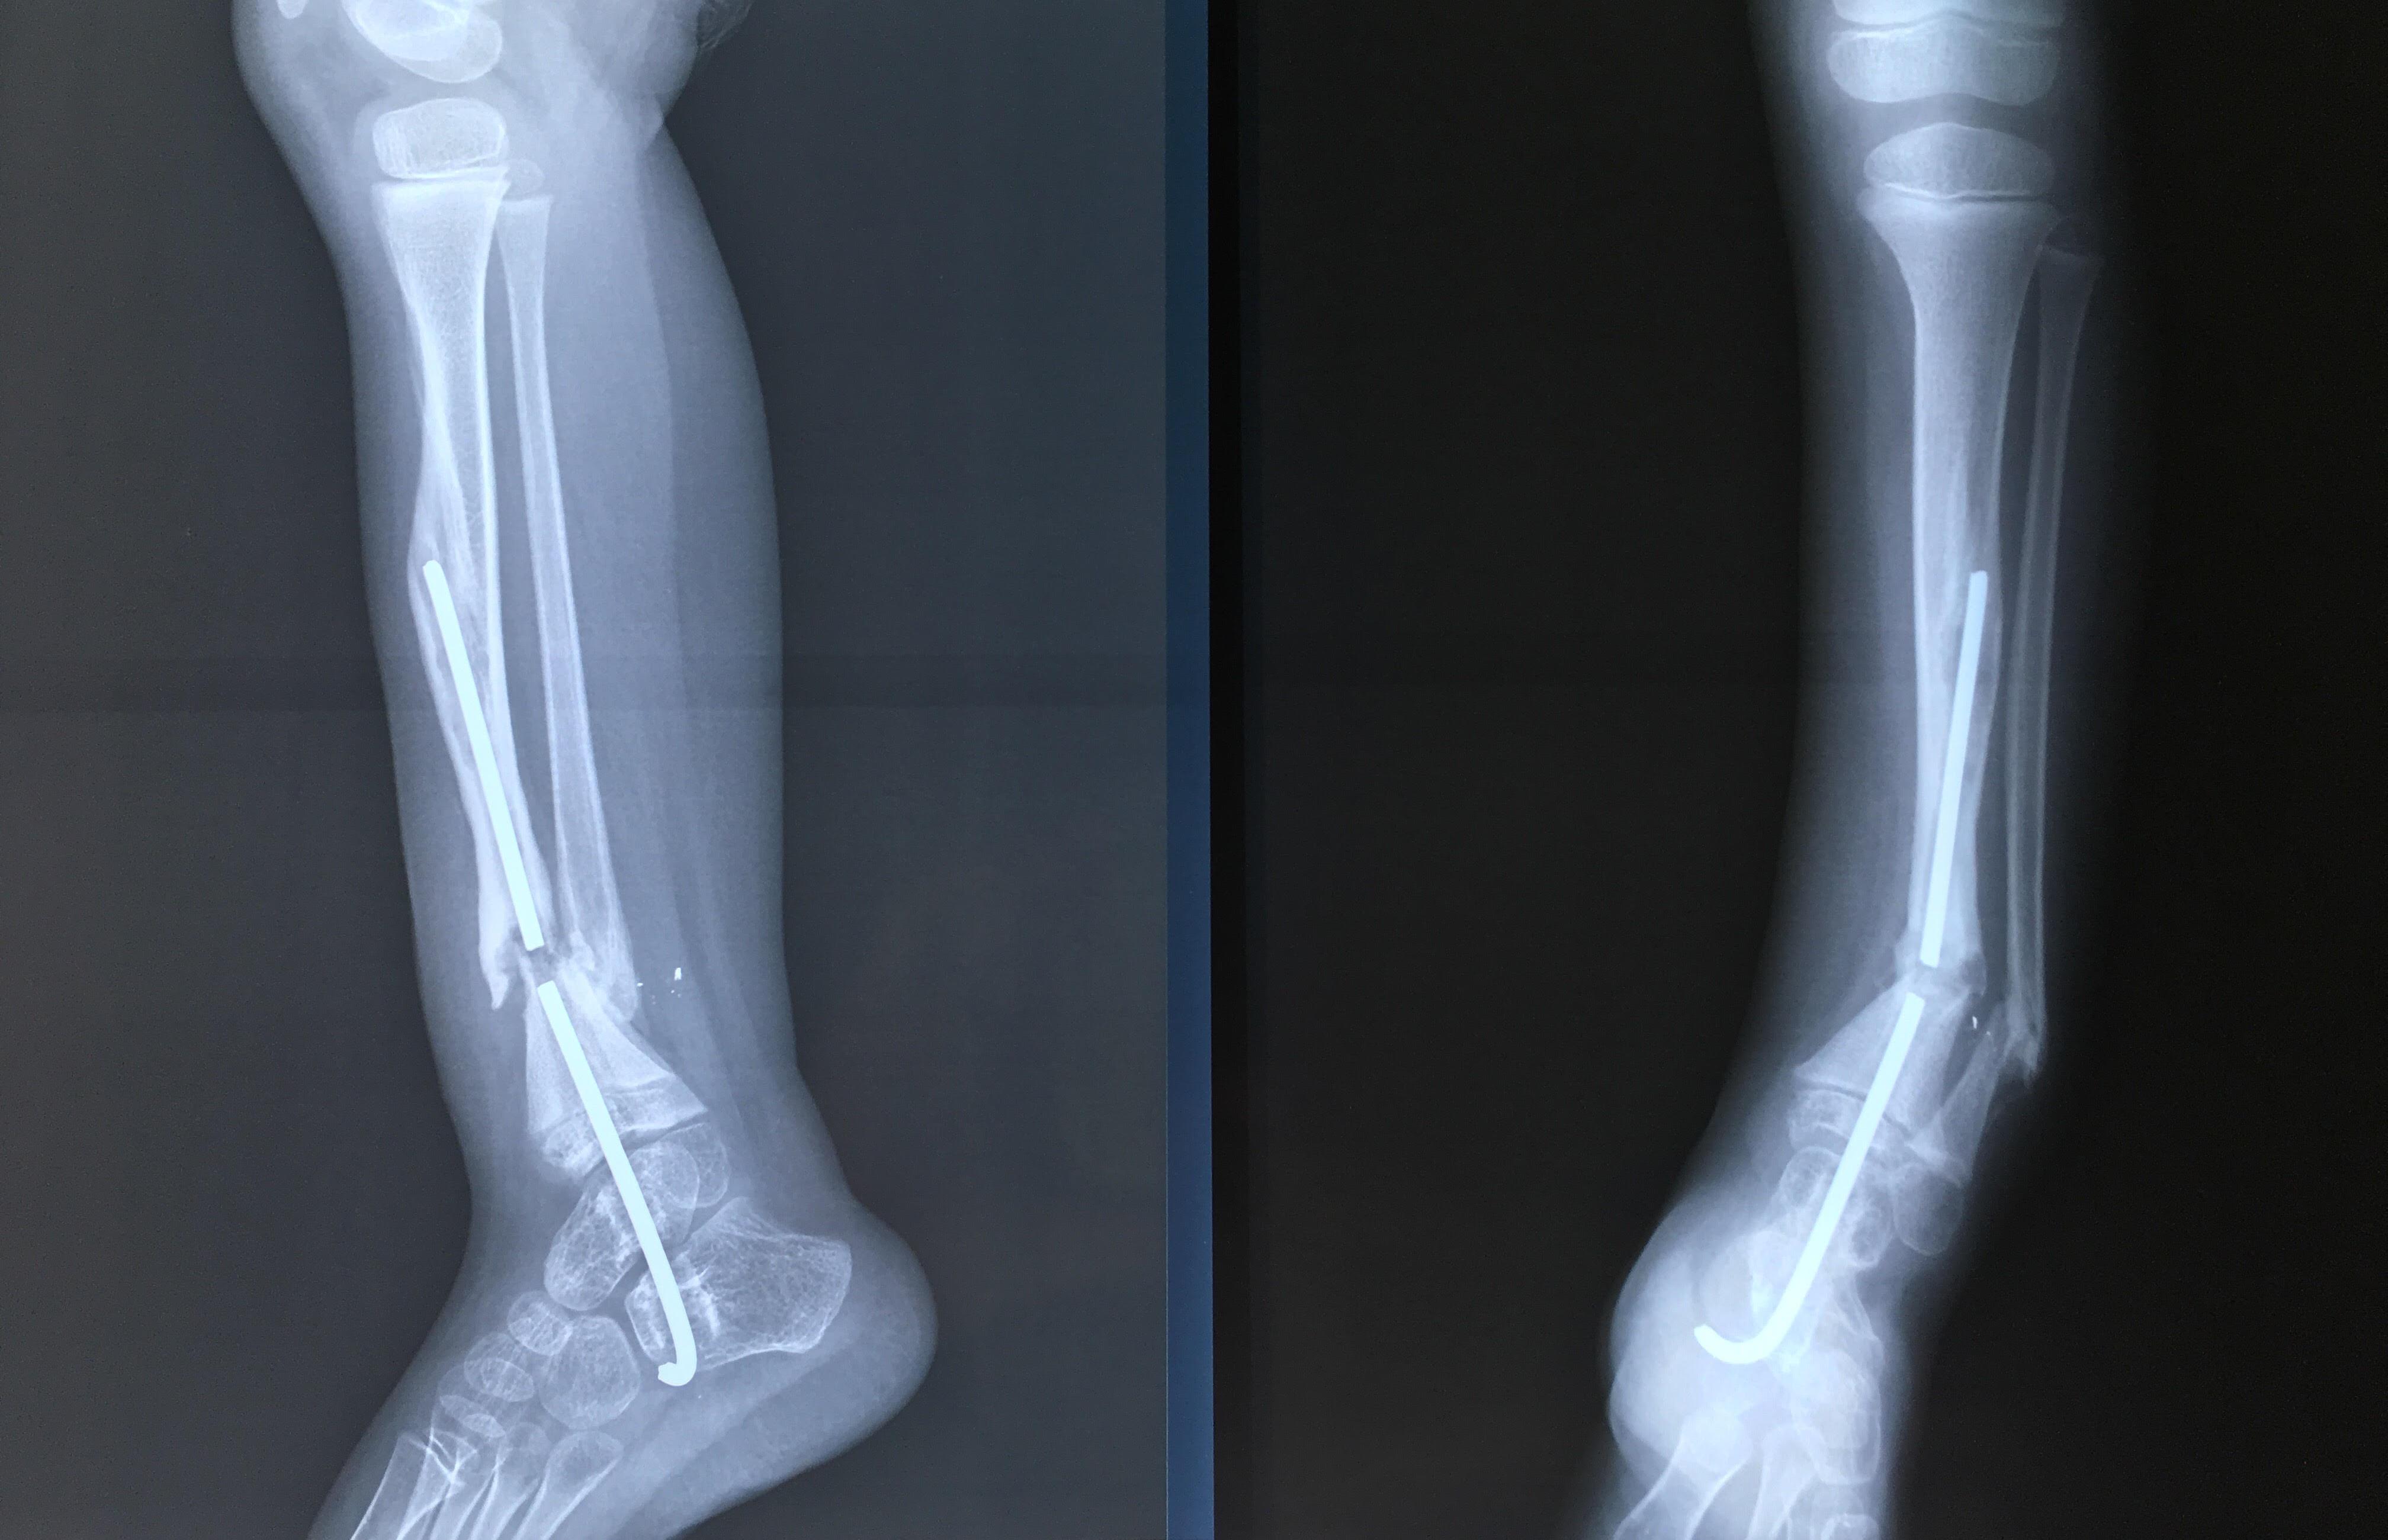

Phẫu thuật thành công ca bệnh hiếm gặp...khớp giả bẩm sinh xương chày

26/06/2019 17:00

Đã xem: 3383

Bệnh viện Chấn thương- Chỉnh hình Nghệ An, vừa phẫu thuật thành công cho bệnh nhi khớp giả bẩm sinh xương chày